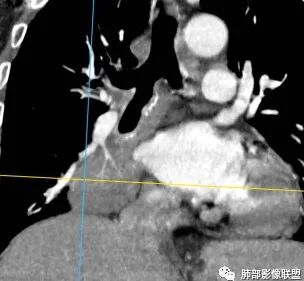

这是支气管,注意看视频支气管连续性的变化。如果上面的支气管完全堵塞,下面的支气管如何解释?

大家考虑这个是支气管腔内占位?引起远端阻塞?还是外围为主病灶侵犯支气管?

南边:个人倾向于外周为主病灶,腔内改变是继发的。原因:病灶围绕支气管,腔内远端无明显阻塞性不张。

边缘偏平直,内部血管走形自然,一般提示包绕为主。

支气管的堵塞也是让我觉得奇怪,当然这种最终支气管镜很直接。

(2)支气管和血管:右肺支气管分支管壁弥漫性增厚,中间段支气管散在结节样凸起,右肺下叶内基底段支气管闭塞,但远端可疑复出。余病灶围绕支气管腔内远端无明显阻塞性不张。内部血管走形自然,提示包绕为主。